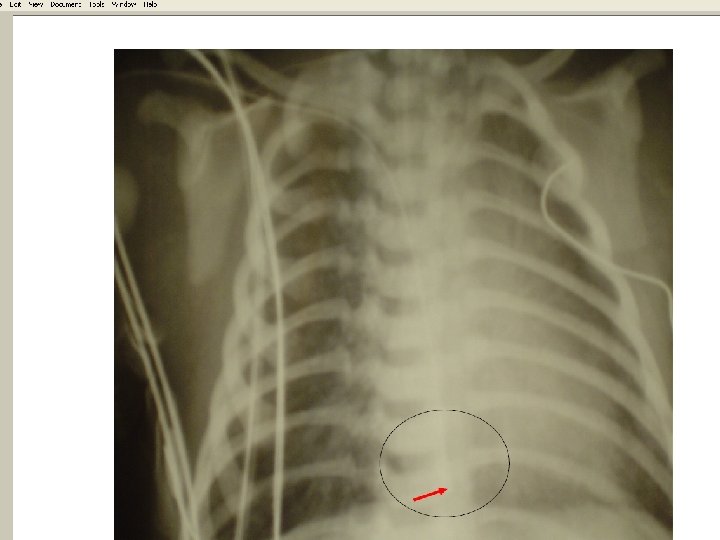

• Types of catheter malposition